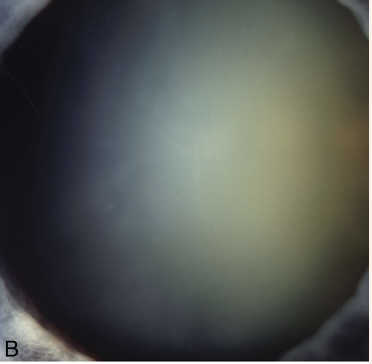

In cataracts, is there a defect in the red reflex?

A

• yes

Cataracts prevent light from getting to the retina, hence you see a defect in the red reflex